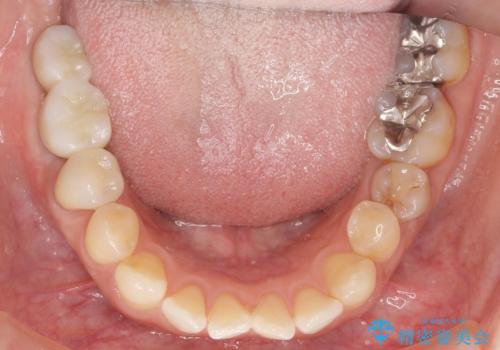

奥歯でしっかり噛むことができるようになり、喜んで頂けました。

セラミッククラウンの審美的な仕上がりにもご満足頂けました。

インプラントの種類:ストローマン BLT

クラウンの種類:ベレッツァクラウン(右下76)、ジルコニアクラウン スタンダード(右下5)